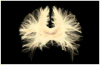

Mild traumatic brain injury (mTBI), also referred to as concussion, remains a controversial diagnosis because the brain often appears quite normal on conventional computed tomography (CT) and magnetic resonance imaging (MRI) scans. Such conventional tools, however, do not adequately depict brain injury in mTBI because they are not sensitive to detecting diffuse axonal injuries (DAI), also described as traumatic axonal injuries (TAI), the major brain injuries in mTBI. Furthermore, for the 15 to 30 % of those diagnosed with mTBI on the basis of cognitive and clinical symptoms, i.e., the "miserable minority," the cognitive and physical symptoms do not resolve following the first 3 months post-injury. Instead, they persist, and in some cases lead to long-term disability. The explanation given for these chronic symptoms, i.e., postconcussive syndrome, particularly in cases where there is no discernible radiological evidence for brain injury, has led some to posit a psychogenic origin. Such attributions are made all the easier since both posttraumatic stress disorder (PTSD) and depression are frequently co-morbid with mTBI. The challenge is thus to use neuroimaging tools that are sensitive to DAI/TAI, such as diffusion tensor imaging (DTI), in order to detect brain injuries in mTBI. Of note here, recent advances in neuroimaging techniques, such as DTI, make it possible to characterize better extant brain abnormalities in mTBI. These advances may lead to the development of biomarkers of injury, as well as to staging of reorganization and reversal of white matter changes following injury, and to the ability to track and to characterize changes in brain injury over time. Such tools will likely be used in future research to evaluate treatment efficacy, given their enhanced sensitivity to alterations in the brain. In this article we review the incidence of mTBI and the importance of characterizing this patient population using objective radiological measures. Evidence is presented for detecting brain abnormalities in mTBI based on studies that use advanced neuroimaging techniques. Taken together, these findings suggest that more sensitive neuroimaging tools improve the detection of brain abnormalities (i.e., diagnosis) in mTBI. These tools will likely also provide important information relevant to outcome (prognosis), as well as play an important role in longitudinal studies that are needed to understand the dynamic nature of brain injury in mTBI. Additionally, summary tables of MRI and DTI findings are included. We believe that the enhanced sensitivity of newer and more advanced neuroimaging techniques for identifying areas of brain damage in mTBI will be important for documenting the biological basis of postconcussive symptoms, which are likely associated with subtle brain alterations, alterations that have heretofore gone undetected due to the lack of sensitivity of earlier neuroimaging techniques. Nonetheless, it is noteworthy to point out that detecting brain abnormalities in mTBI does not mean that other disorders of a more psychogenic origin are not co-morbid with mTBI and equally important to treat. They arguably are. The controversy of psychogenic versus physiogenic, however, is not productive because the psychogenic view does not carefully consider the limitations of conventional neuroimaging techniques in detecting subtle brain injuries in mTBI, and the physiogenic view does not carefully consider the fact that PTSD and depression, and other co-morbid conditions, may be present in those suffering from mTBI. Finally, we end with a discussion of future directions in research that will lead to the improved care of patients diagnosed with mTBI.